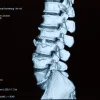

Radiology reading rooms are intentionally dim to optimise image contrast and reduce glare, supporting accurate interpretation. However, prolonged time in such settings coincides with reduce